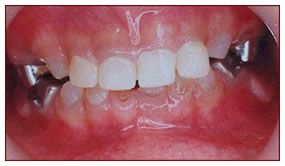

Composite Filling

Teeth affected by decay or trauma are restored with tooth coloured composite material.

Composite Filling with Strip Crown